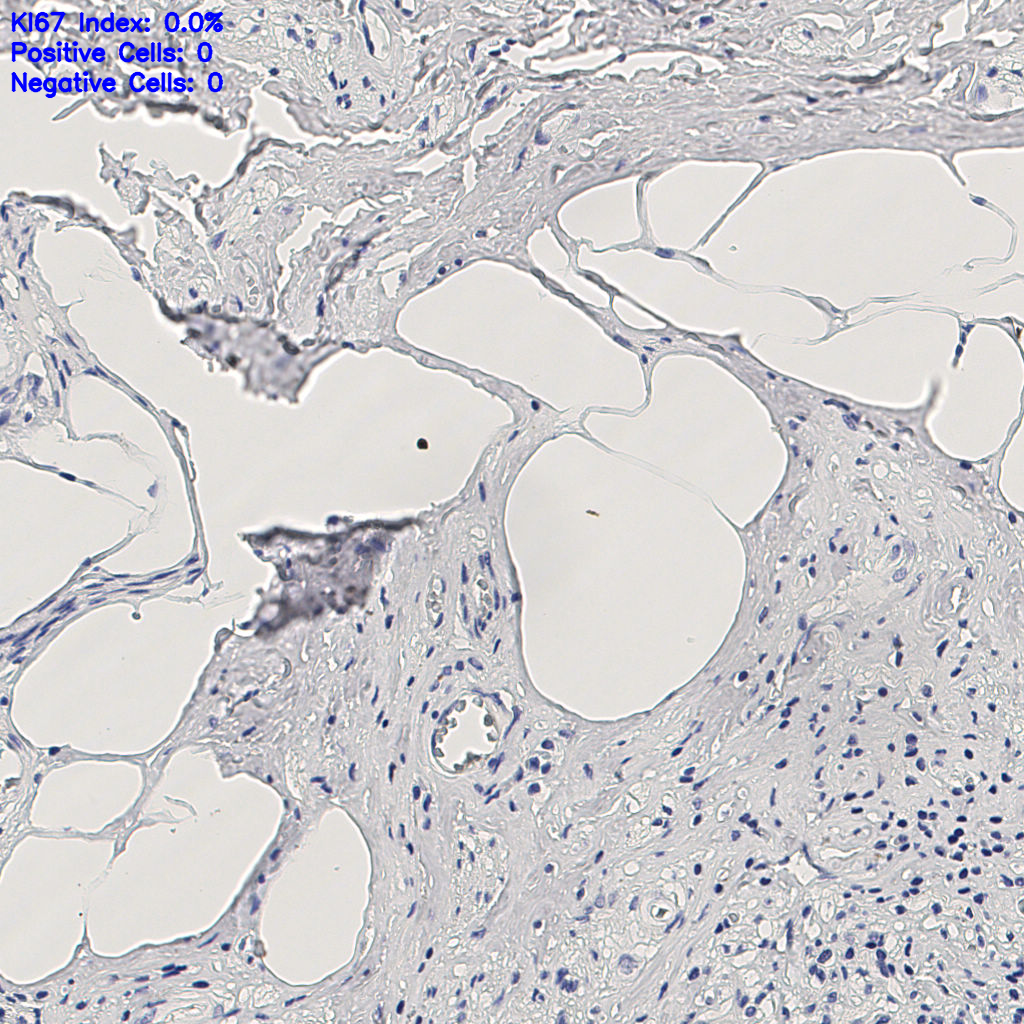

缩略图

slice_7_23_x6272_...

标记后

标记前